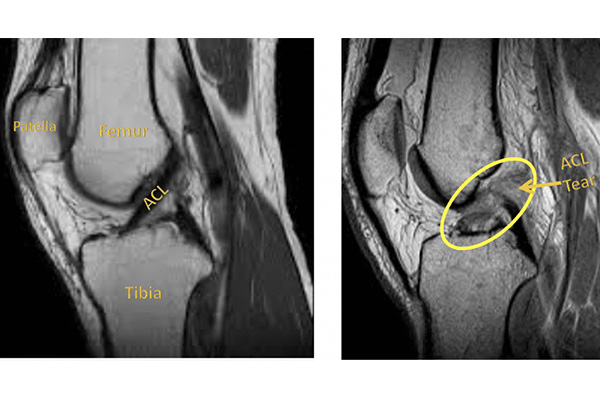

The decision to choose an ACL graft can be overwhelming. This week, we will focus on the pros and cons of the major graft options & share new resources that we put together for The Sports Docs Podcast on this topic.

Which ACL graft is best for me?

There are many graft options to choose from and we discuss the pros/cons of each choice in this episode!